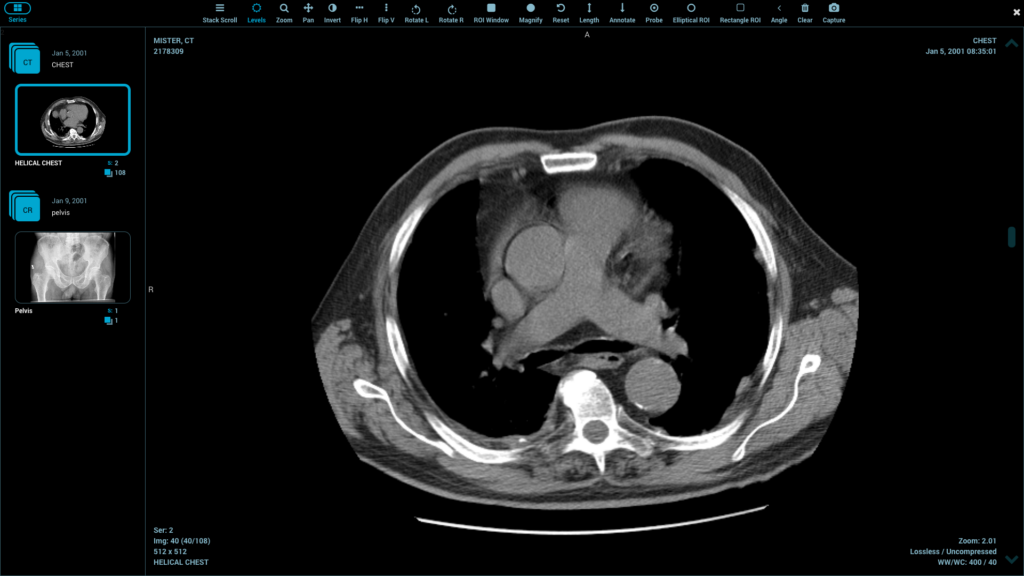

Healthcare software ecosystems are vital because of seamless integration. The components of the DICOM viewer library should be able to interface well with PACS and RIS platforms. Integration with electronic health records helps to facilitate a single workflow.